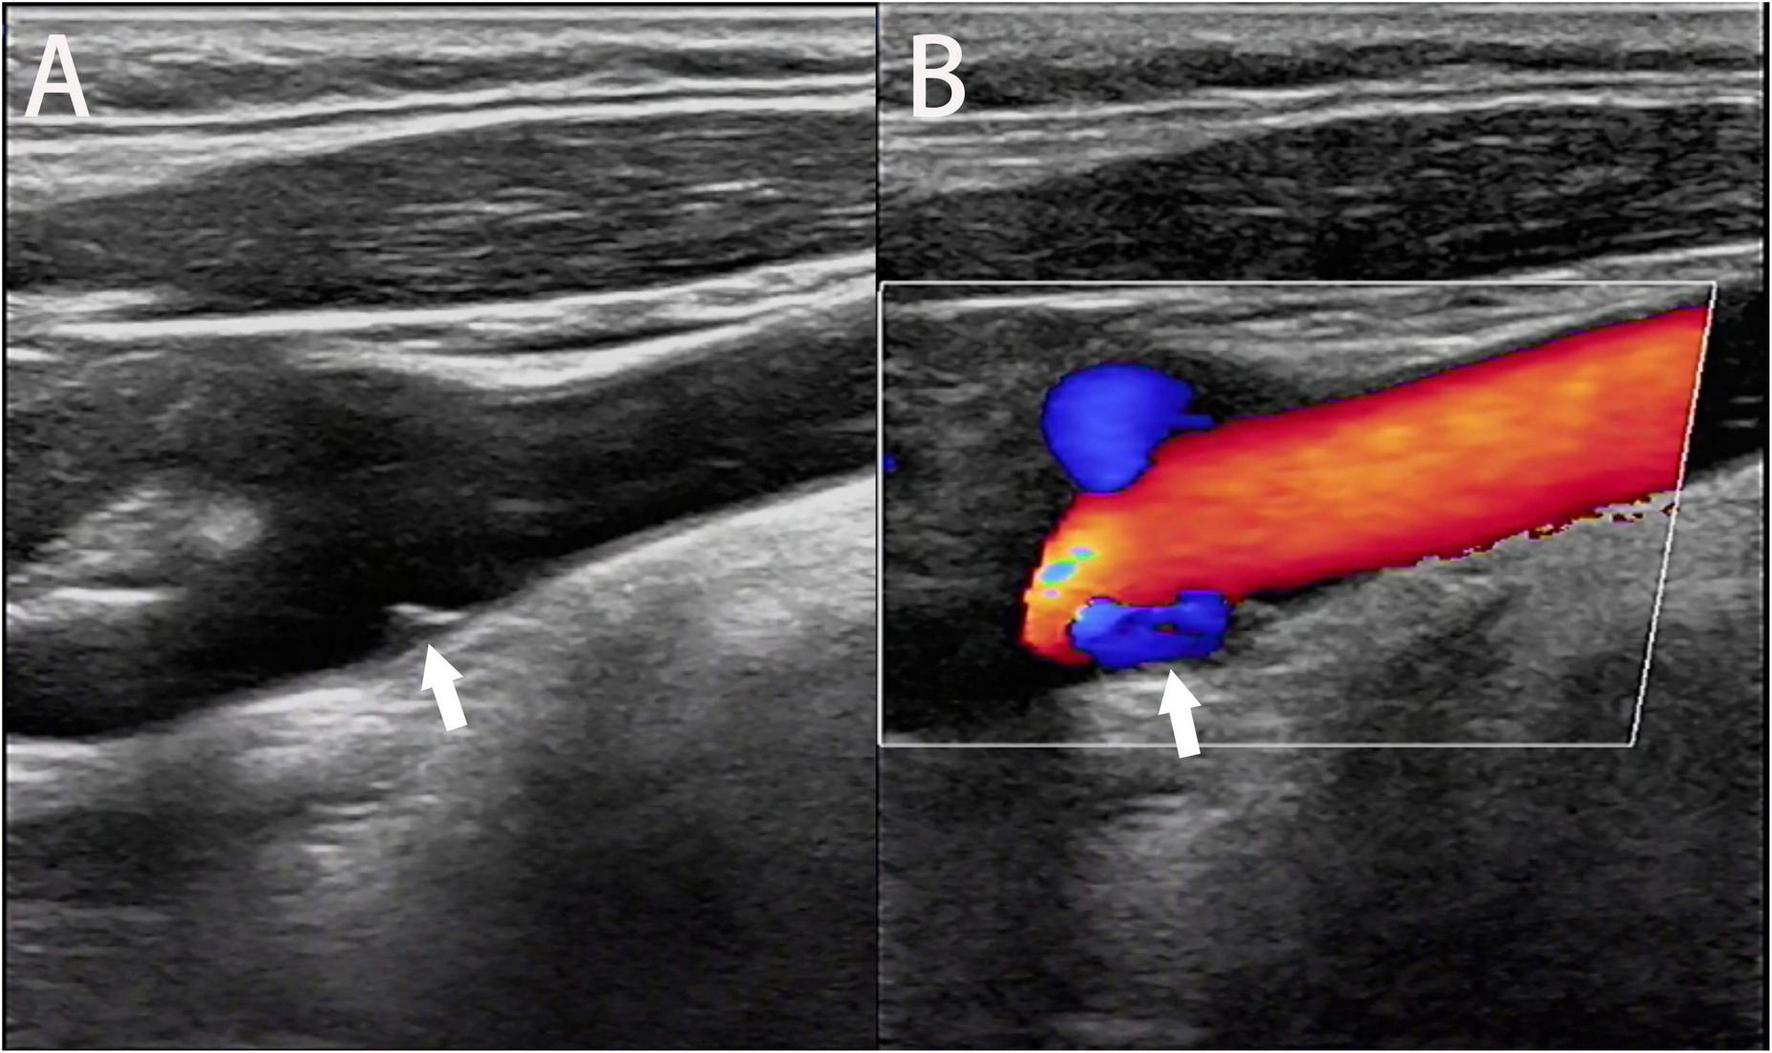

During routine ultrasound, the carotid web presents as a film-like structure that is isoechoic or hypoechoic and originates from the vessel wall of the carotid artery and protrudes into the lumen with or without peripheral atherosclerosis (Fontaine et al., 2022; Figure 5A). Additionally, it generally presents with “cliff-like” arterial stenosis in the longitudinal section (Ben et al., 2022), which is superior to the manifestation in the transverse section in terms of the carotid web diagnosis. Using the color Doppler, an eddy can be found at the angle between the carotid web and vessel wall (Phair et al., 2017; Figure 5B). Routine ultrasound performed to diagnose the carotid web is convenient and safe; however, it may lead to misdiagnoses, including carotid dissection and ulcerative plaque. Therefore, multiple techniques, such as three-dimensional ultrasound imaging, contrast-enhanced ultrasonography, and intravascular ultrasound, have been developed as alternatives to routine ultrasound to reduce the misdiagnosis rate. Three-dimensional ultrasound imaging can depict the anatomical structure of the carotid web using three-dimensional multiplanar reconstruction (Gao et al., 2022). Contrast agent infusion delays and filling defects were observed using contrast-enhanced ultrasonography (Zhou et al., 2022). Intravascular ultrasound provides a dynamic view of the vessel lumen using an ultrasonic mini-probe with a catheter technique, and the carotid web presents with a banding hypoechoic signal connecting to the vessel wall (Hassani et al., 2020).

FIGURE 5

Ultrasonic image of the longitudinal section shows the carotid web extending into the lumen of the carotid bulb (A, arrow). An eddy current is generated at the angle between the carotid web and the artery wall on the color Doppler flow image (B, arrow).